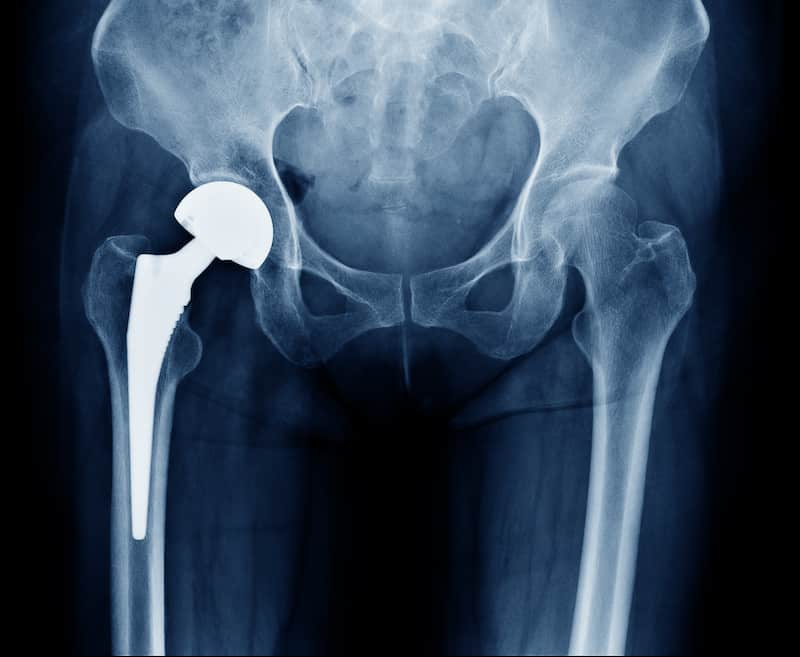

Joint Replacement Surgery

These pages are designed to give you the right information about some common joint replacement surgeries, along with some advice and exercises to help you with your rehabilitation.